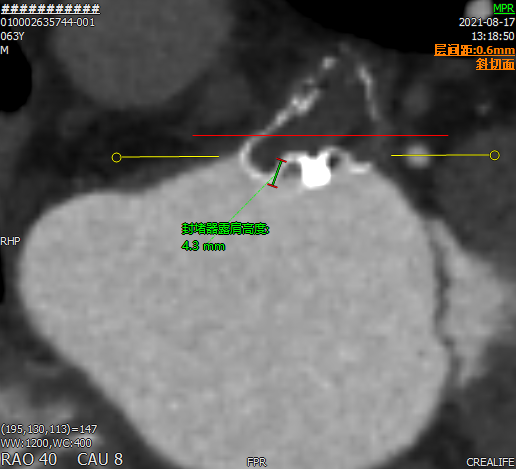

术前CT评估

行CT评估后左心耳内未见血栓,左心耳呈反鸡翅型,开口呈椭圆形,最短径17.3mm,最长径 21.7mm,三维深度19.1mm,二维深度 18.0mm。分析后提示宜选择24mm Watchman封堵器,但若采用下叶进行封堵,深度较浅,应首选上叶做为轴线进行封堵。

采用CT模拟最佳左心耳封堵工作体位,发现在RAO30 CAU25时左心耳展开较常规体位更好。

患者TEE检查心耳内无血栓,TEE提示为反鸡翅可能,CTA重建心耳后为反鸡翅型,根据术前入路模拟,考虑穿刺点应偏下稍靠前,根据心脏CT及TEE评估结果来看,左心耳梳状肌发达,开口椭圆形,直径17mm-21mm,考虑24mm WATCHMAN封堵植入,在封堵轴线选择上应以上叶为首选。

术后2个月CT三维重建,直观查看封堵器植入形态,且从二维图像来看,未见残余分流。

术后

封堵后透明三维

术后2个月未完全内皮化,未见DRT。

CT随访后提示左心耳封堵完全,遂停用达比加群,予以双联抗血小板药物进行治疗。